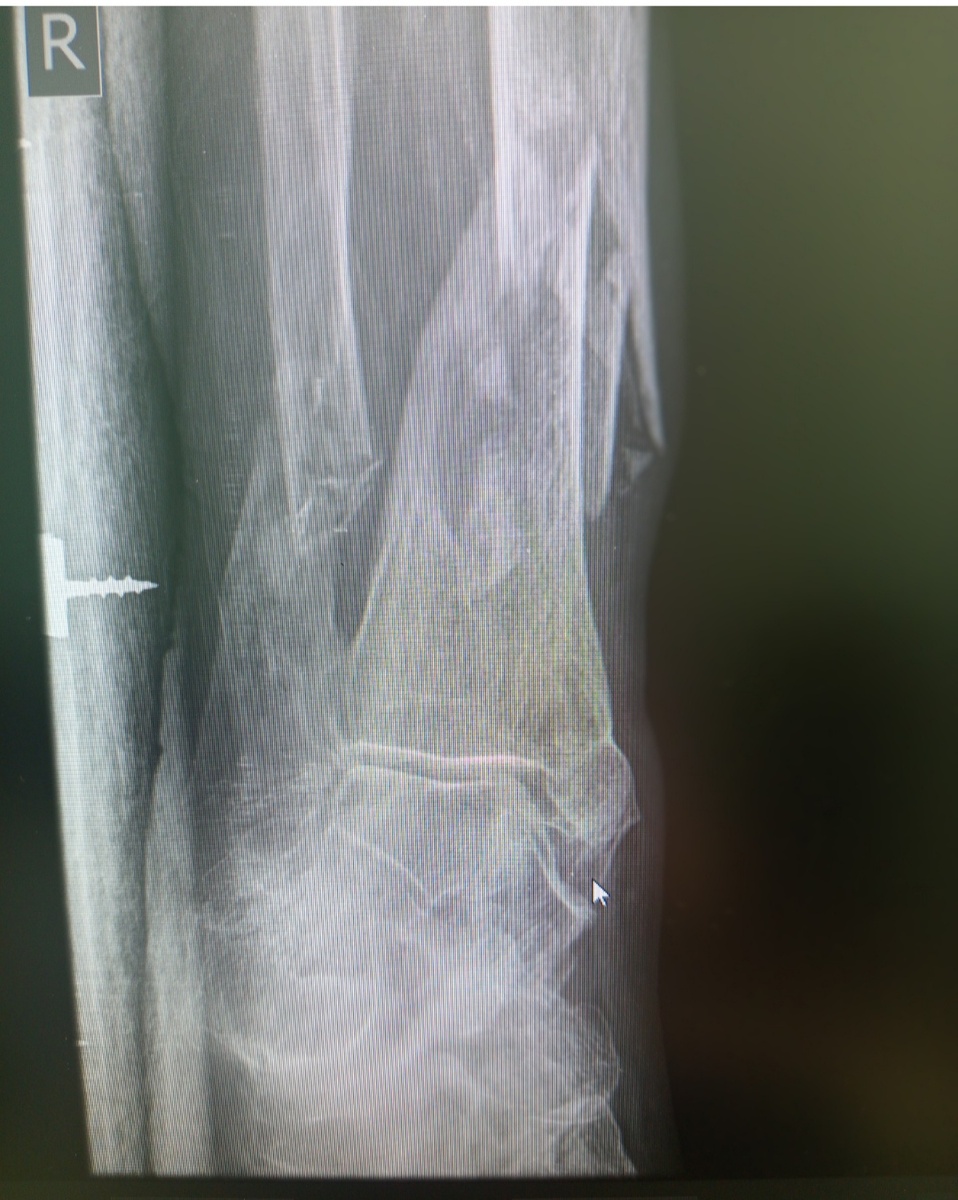

Бабушка глуховата, но почему-то активна. Назначили легкие и голеностоп.

Она шевелит активно ногой так , что мне кажется , что перелом из закрытого превратится в открытый.

Но , не случилось к счастью.

И буквально сразу , через пару пациентов завезли молодого парня .26 лет.Упал на тренировке с дорожки.

-3